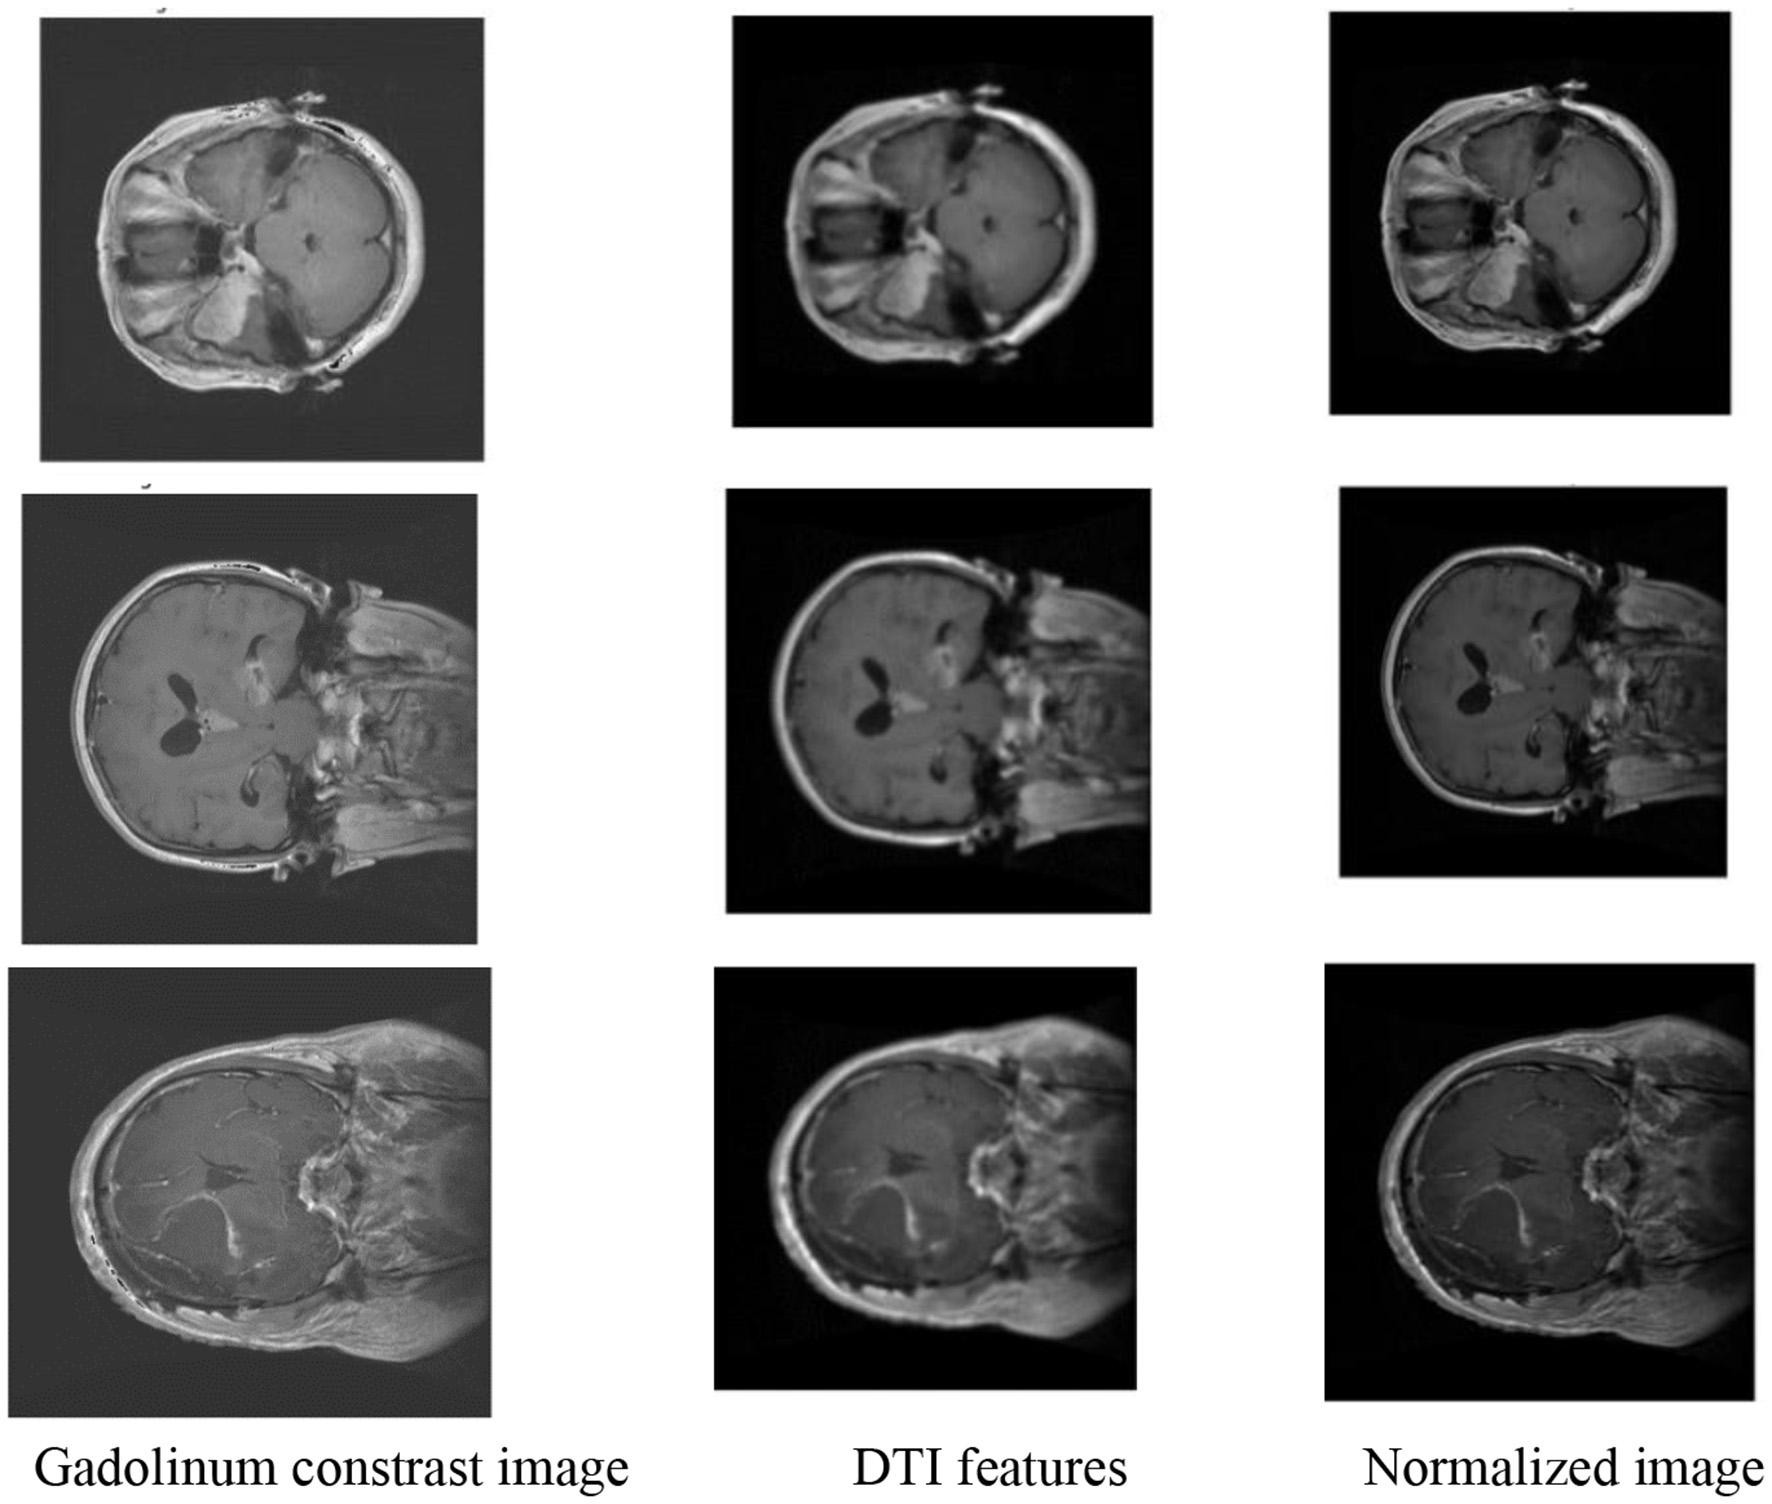

In this step, we utilize the PVT augmented with a Deformable Attention mechanism to extract discriminative features from pre-processed BT images. The PVT architecture, known for its patch-based processing and global contextual understanding, is enhanced by deformable attention, which dynamically adjusts receptive fields to focus on informative regions within the image. This approach enables the model to capture a diverse set of deep features essential for differentiating gliomas, meningiomas, and pituitary tumors. These features include image intensity, texture, shape, size, location, enhancement patterns, DTI features such as FA and MD, and radiomics features. Gliomas, with their high water content, appear hyperintense on T2-weighted MRI images, whereas meningiomas are typically isointense or slightly hypointense. Irregular tumor shapes and locations, such as gliomas being found anywhere in the brain, meningiomas near the meninges, and pituitary tumors at the base of the brain, further distinguish the tumor types. Gliomas often show gadolinium enhancement, while meningiomas may not, and pituitary tumors typically do not enhance. DTI features also play a critical role, as gliomas typically display lower FA and higher MD, meningiomas show higher FA and lower MD, and pituitary tumors exhibit varying FA and MD. The deformable attention mechanism, with adaptive sampling and hierarchical dynamic position embeddings, enables the model to focus on relevant regions and better fuse features, improving the model's ability to classify complex tumor types with higher accuracy. The Gadolinium contrast and DTI features in an MRI image is depicted in Figure 2.

The presented Figure 5 provides a details of the advanced stages of the proposed methodology for BT classification, specifically focusing on images enhanced with gadolinium contrast and incorporating DTI features. The image with gadolinium contrast and DTI features encapsulates crucial diagnostic information, showcasing the distinctive enhancement achieved through gadolinium contrast, a hallmark of certain BT types. This enhancement aids in emphasizing specific characteristics, such as increased vascularity crucial for accurate classification. Additionally, the incorporation of DTI features, including FA and MD, further enriches the feature set. These features play a pivotal role in capturing nuances related to tissue microstructure and water diffusion within the brain. The normalized output complements this by illustrating the refined and standardized representation of these enhanced features, ensuring consistency and facilitating robust feature extraction.